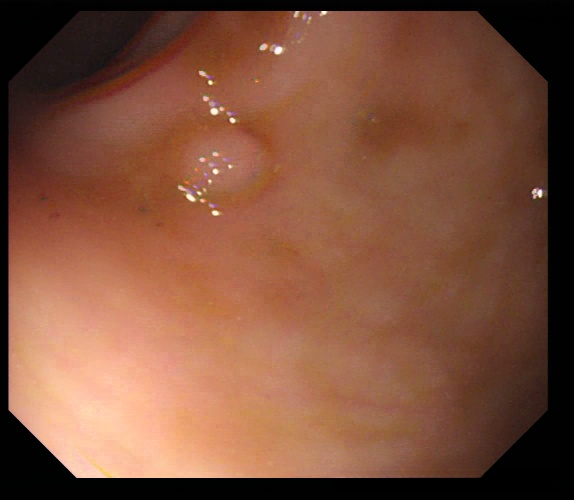

3、ETIS : ETIS(Eurecom Thermal Imaging and Segmentation)数据集旨在利用热成像技术实现结肠息肉的检测。该数据集提供了热成像图像,并对其中的相关结肠息肉进行了标注。这些标注内容有助于研究者进一步探索热成像技术在结肠息肉检测中的应用价值。

处理好后的COCO格式的数据集图像的总数为196张,类型标签为病灶区域。